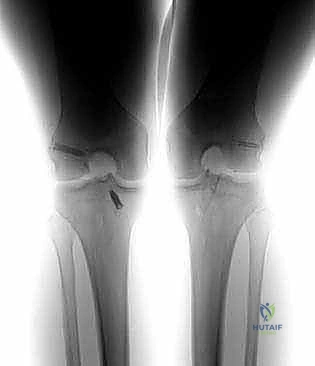

* الأشعة السينية (X-rays): ضرورية لتقييم اتساع الأنفاق العظمية السابقة (Tunnel Widening)، مواقع مسامير التثبيت القديمة، ووجود أي علامات لخشونة المفصل أو انحراف محوري.

* الأشعة المقطعية (CT Scan): في حالات الفشل الجراحي، تعتبر الأشعة المقطعية السلاح الأهم. فهي توفر نمذجة ثلاثية الأبعاد (3D) دقيقة جداً لمواقع الأنفاق العظمية القديمة وحجمها، مما يساعد الدكتور هطيف في اتخاذ قرار حاسم: هل يمكن حفر أنفاق جديدة فوراً، أم يجب إجراء الجراحة على مرحلتين؟